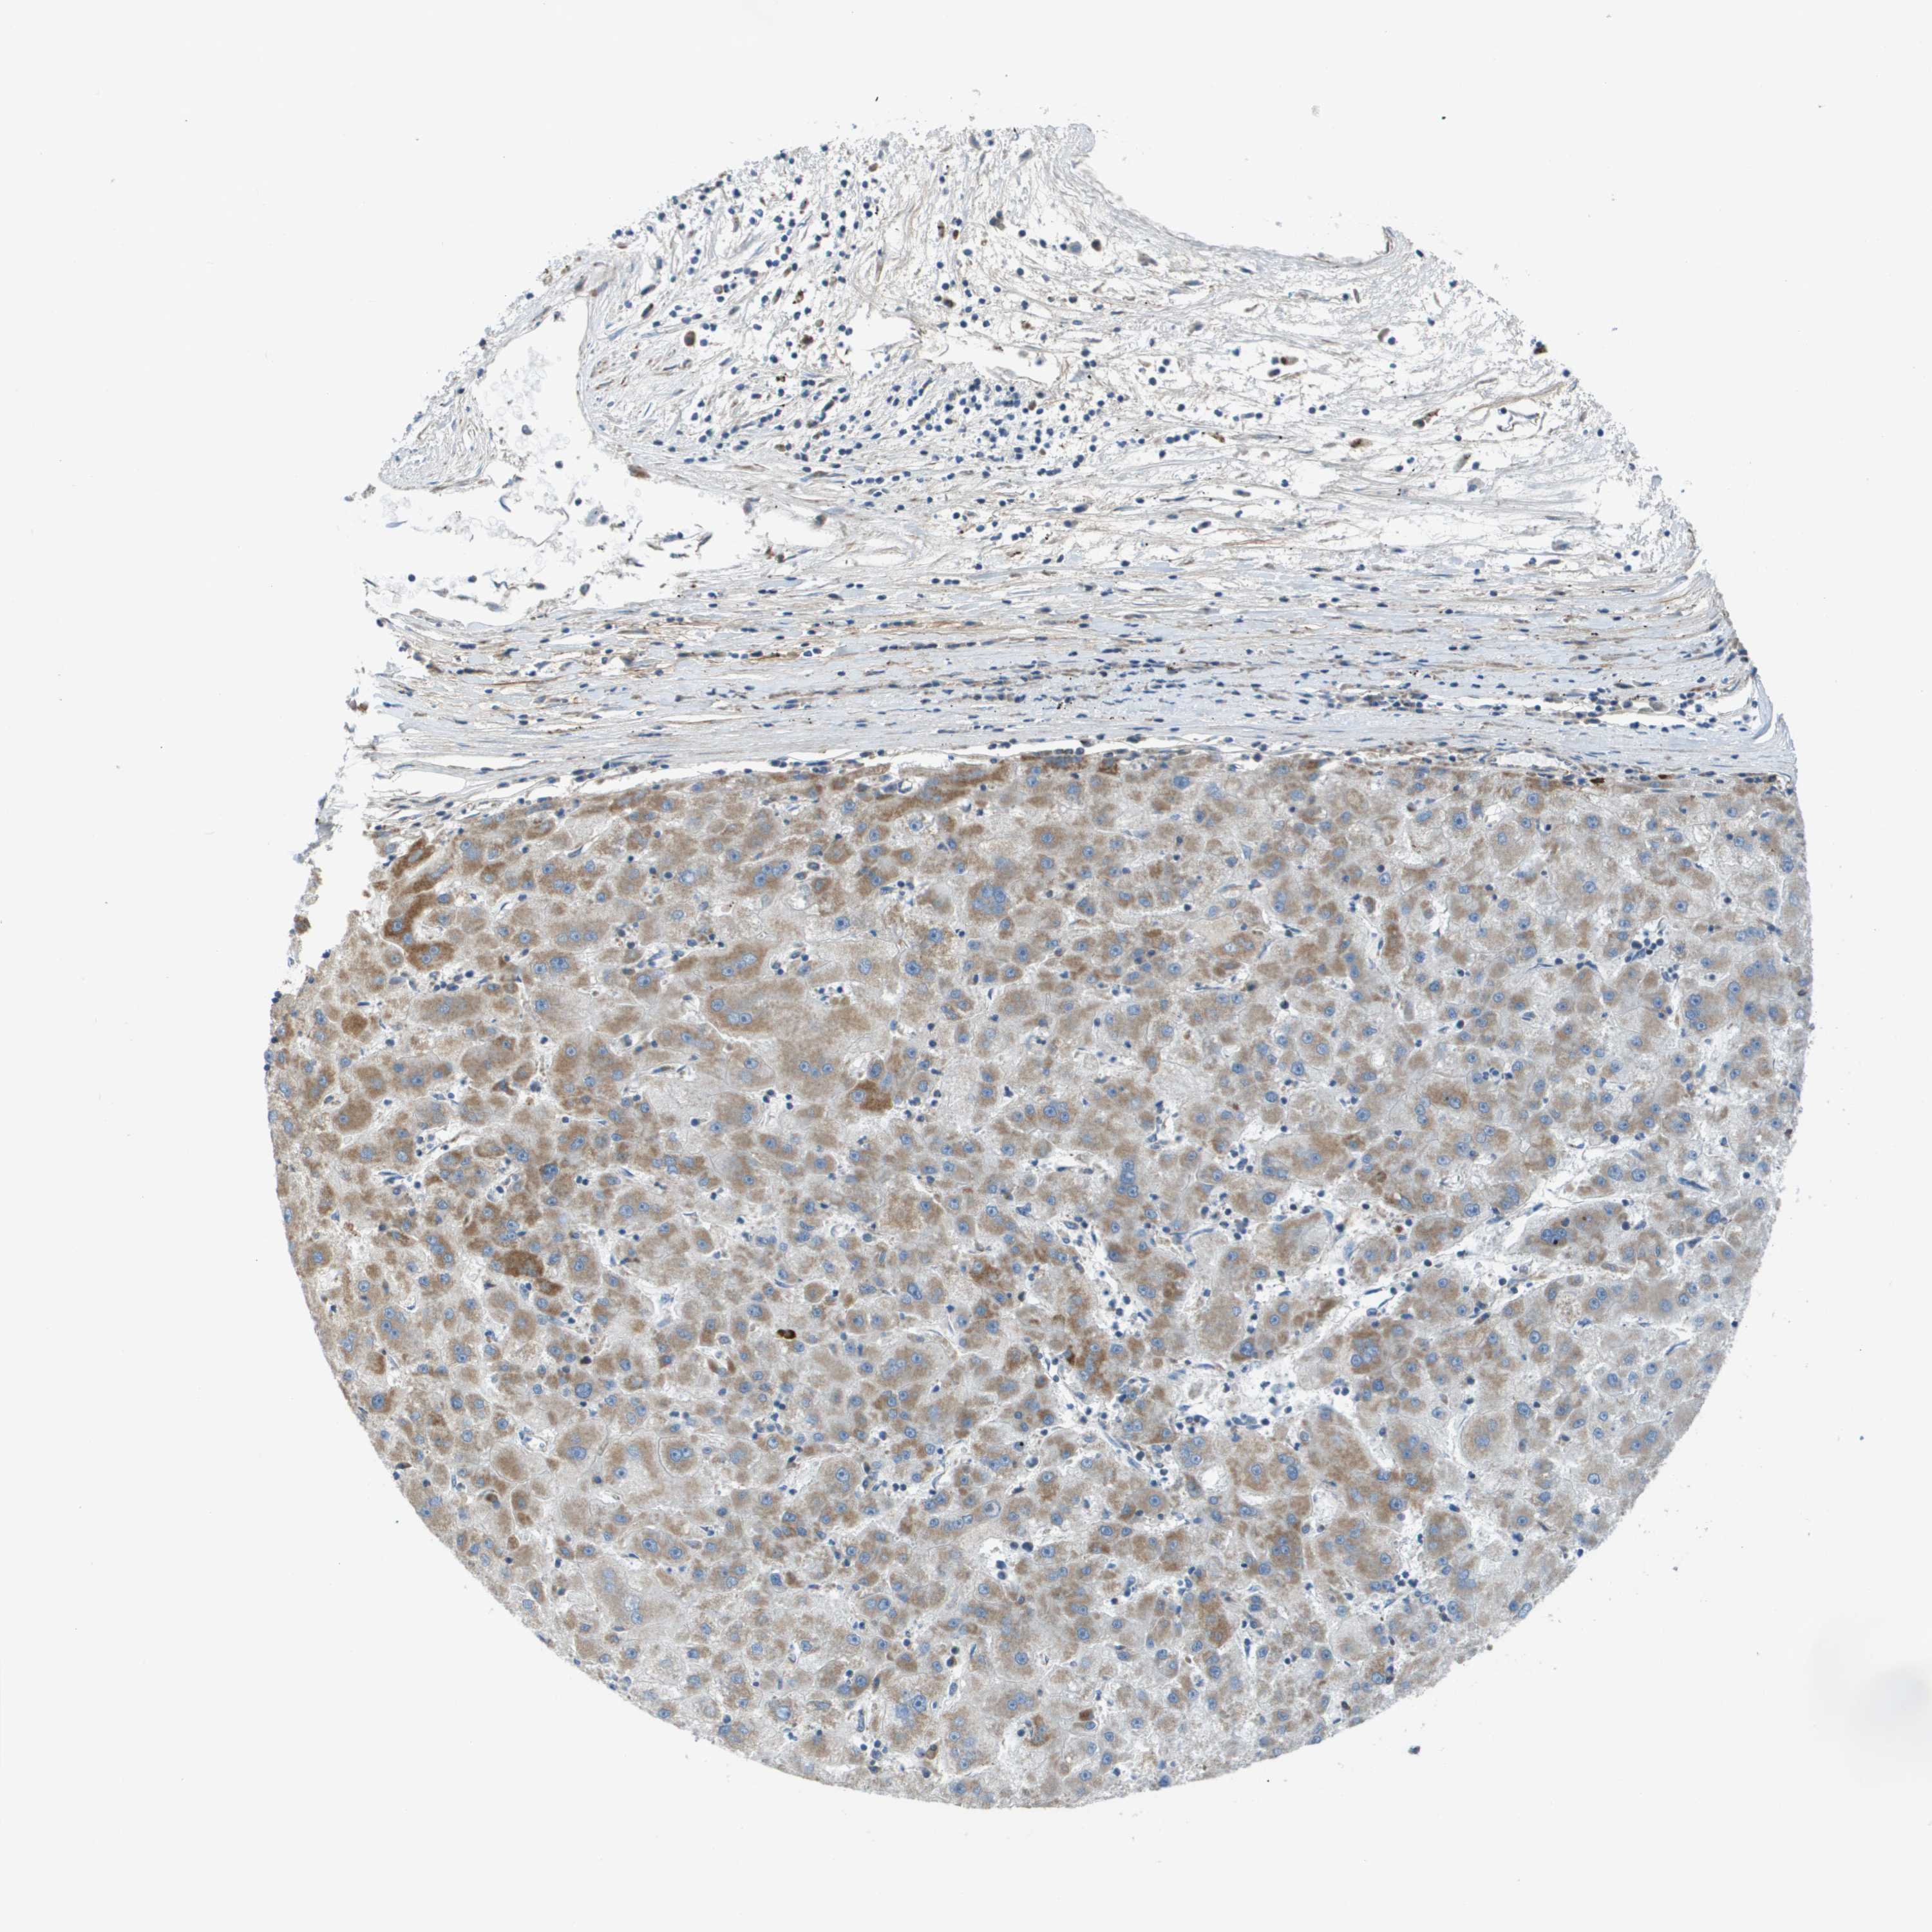

LIVER CANCER - Protein expressioni

A mouse-over function shows sample information and annotation data. Click on an image to view it in a full screen mode. Samples can be filtered based on level of antibody staining by selecting one or several of the following categories: high, medium, low and not detected. The assay and annotation is described here.

Note that samples used for immunohistochemistry by the Human Protein Atlas do not correspond to samples in the TCGA dataset.

Antibody stainingi

Antibody staining in the annotated cell types in the current human tissue is reported as not detected, low, medium, or high, based on conventional immunohistochemistry profiling in selected tissues. This score is based on the combination of the staining intensity and fraction of stained cells.

Each image is clickable and will lead to virtual microscopy that enables deeper exploration of all samples and also displays staining intensity scores, fraction scores and subcellular localization as well as patient and tissue information for each sample.

Antibody HPA011762

Antibody HPA017086

Staining

High

Medium

Low

Not detected

Intensity

Strong

Moderate

Weak

Negative

Quantity

>75%

75%-25%

<25%

None

Location

Nuclear

Cytoplasmic/membranous

Cytoplasmic/membranous,nuclear

Cholangiocarcinoma

Carcinoma, Hepatocellular, NOS